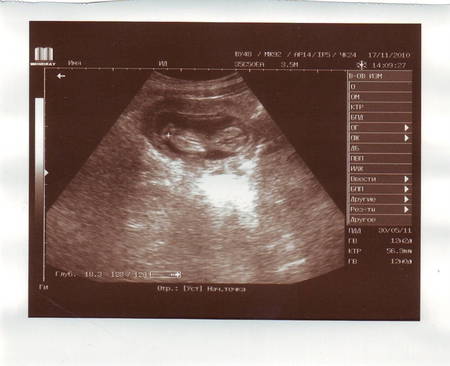

Результаты: УЗИ, КТГ, доплера, скринингаПривет девочки!! вчера первый раз ходили на УЗИ и еще на учет вставать!! так вот с малышом все в порядке, врач сказала что на таком сроке уже видно пол и хотела нам сказать но наш малыш прикрылся ножкой. правда одно меня смущает, у меня тонус!! вот сегодня иду сдавать анализы, посмотрим что скажут. а я до ужаса боюсь уколов!!!!!

А вот и наш первый снимок: